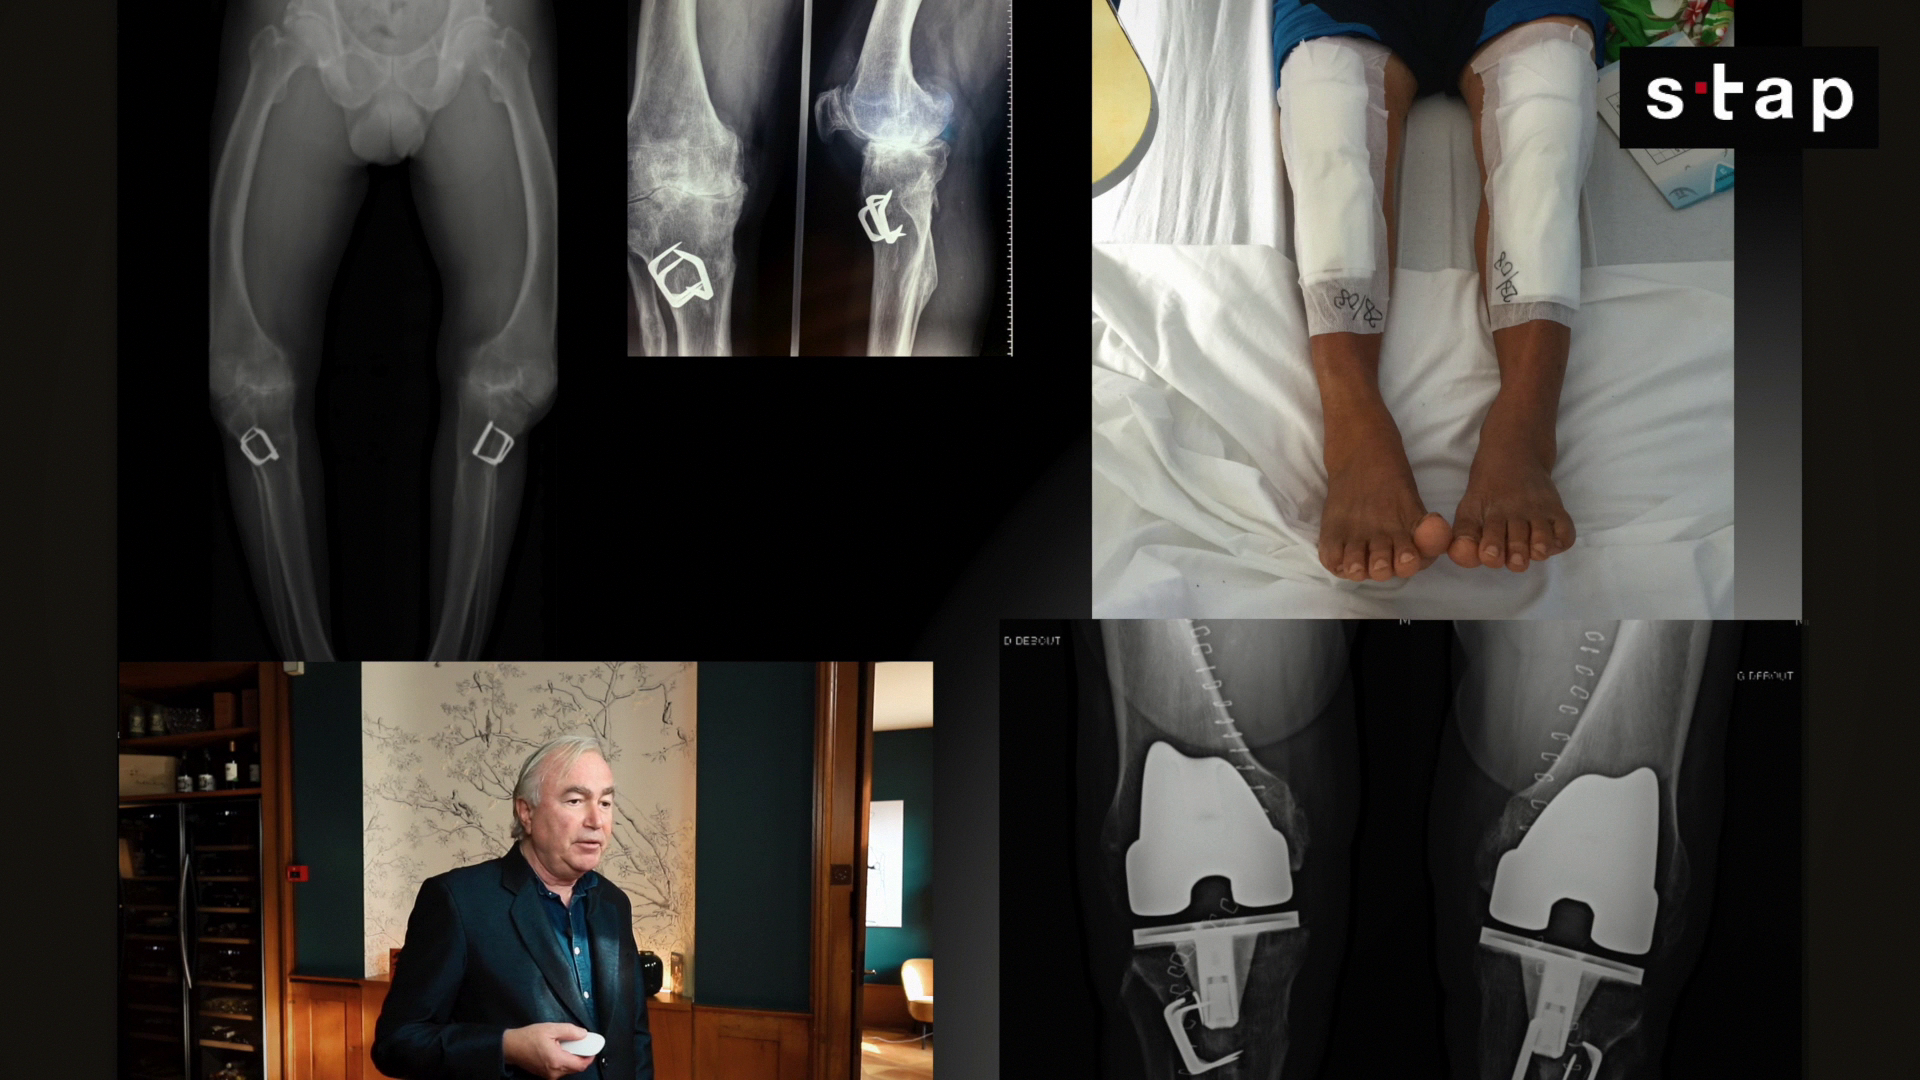

Comment choisir une prothèse totale de genou de première intention

Aujourd'hui, j'aimerais aborder un sujet qui, pour reprendre les mots de Talleyrand, "va sans dire, mais va mieux en le disant" : comment choisir une prothèse totale du genou de première intention. Fort de plusieurs publications et d'une certaine expérience, je souhaite partager quelques idées de bon sens qui pourraient éclairer ce choix crucial.

Choisir sa Prothèse Totale du Genou :

Au-delà des Idées Reçues

1. Le Choix de l'Implant Lui-même : Versatilité et Adaptabilité

- Gamme Étendue : Faire partie d'une large gamme d'implants pour éviter l'« oversizing » (prothèse trop grande) et assurer un ratio médiolatéral adapté, notamment pour les petites tailles. La prothèse U2 est citée comme exemple, ayant un bon design et une large gamme d'implants.

En somme, il est plus important de réaliser une indication personnalisée et adaptée sur mesure pour le patient qu'un implant fait sur mesure.